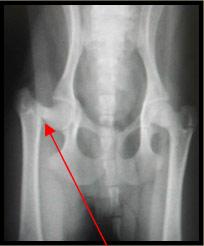

Fracture du col fémoral

Votre animal s’est fracturé l’os de la cuisse à l’endroit où celui-ci s’articule avec le bassin. Un plâtre n’a pu être mis en place pour stabiliser la fracture parce qu’il est impossible d’immobiliser la hanche. Nous avons donc dû retirer chirurgicalement le morceau de fémur qui était encore attaché à la hanche.